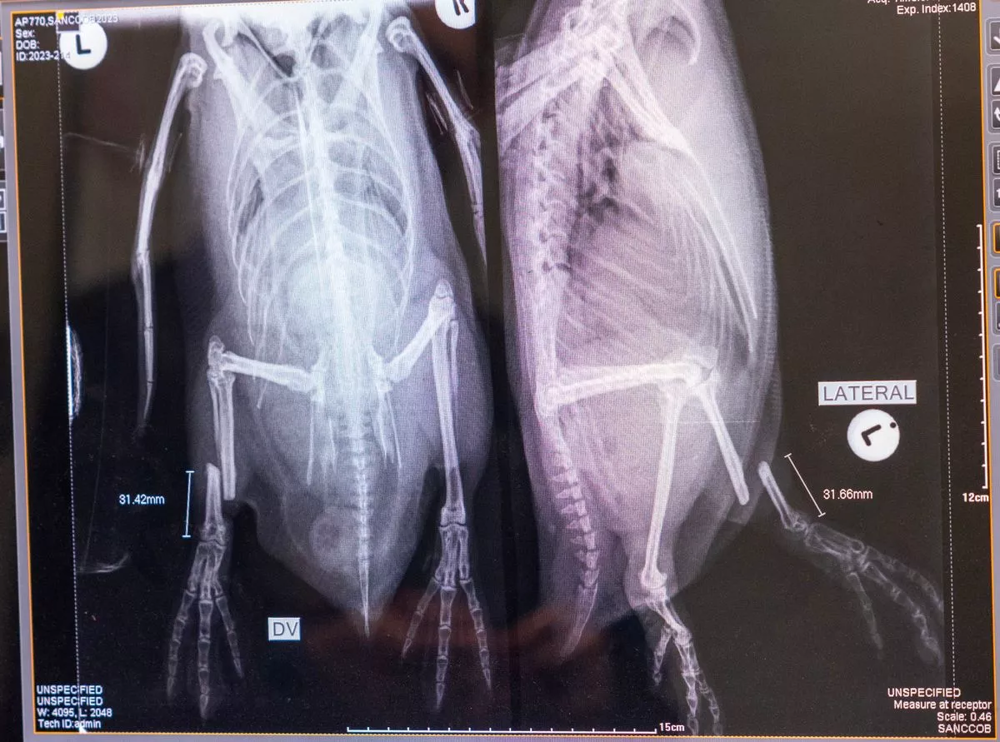

Південноафриканський фонд збереження прибережних птахів SANCCOB у Кейптауні займається лікуванням поранених, покинутих, хворих або постраждалих від розливів нафти пінгвінів. Серед них – очкові пінгвіни, які перебувають під загрозою зникнення. Ці птахи почали зникати після подвійного удару — надмірного вилову риби та зміни клімату. Вчені стверджують, що якщо не вжити термінових заходів, африканські пінгвіни зникнуть до 2035 року, і в Південній Африці залишиться всього 8 300 пар, що розмножуються. Щорічно у шпиталі виходжують у середньому 500-600 пташенят африканських пінгвінів та 300-400 яєць, і з кожним роком їх кількість зростає.

Цього року співробітники південноафриканського центру подбали про 279 африканських пінгвінів. Основне завдання центру порятунку - врятувати слабких птахів із дикої природи, відновити їхнє здоров'я та випустити назад, щоб вони успішно продовжували рід. Так фахівці намагаються зберегти населення. Деякі з пінгвінів після прибуття до центру порятунку страшенно виснажені, у них уповільнений серцевий ритм, а у багатьох трапляються проблеми з легенями. Одним пінгвінам ставлять крапельниці і переливають кров, якщо це необхідно, крихітних пташенят годують сардинами кожні дві години, роблять інші процедури і всіляко піклуються про них.